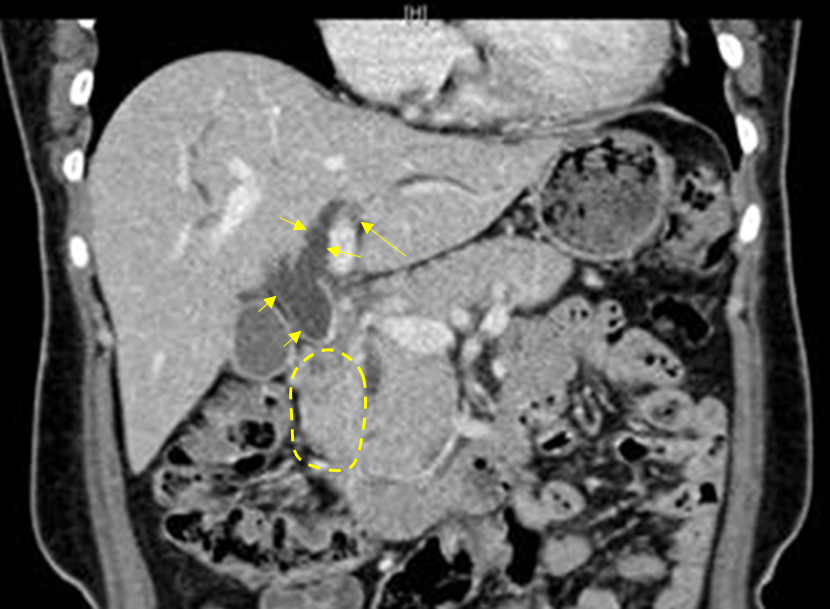

Img | CT: Periampullary mass MRCP: CBD mass, proximal CBD dilatation |

폐쇄성 황달, CA 19-9 상승, CT상 periampullary mass, MRCP상 CBD가 중간에 좁아진 소견이 있으므로 담관암이 가장 의심된다.

• 담도 폐쇄의 원인을 확인하기 위해 촬영한 CT상 CBD와 췌장이 있는 곳에 커다란 mass가 관찰된다. MRCP상 CBD의 중간 부분이 조영되지 않으며, 그보다 distal한 부분은 조영되고, proximal한 부분은 dilatation이 있다. 따라서 췌장암보다는 담도암으로 보인다.

• 췌장암: 췌두부암의 경우 폐쇄성 황달과 CA 19-9 상승이 나타날 수 있으나, 본 증례의 MRCP상 CBD의 가운데 부분이 조영되지 않으므로, 이곳이 mass의 위치로 생각된다. 만약 췌두부암이었다면 조영제가 들어오는 distal CBD 쪽이 조영되지 않았을 것이다.

• 파터팽대암: 폐쇄성 황달을 나타낼 수 있으나, MRCP에서 CBD 중간만 조영되지 않는 소견은 나타나기 어려웠을 것이다.